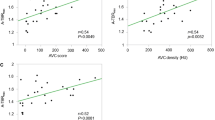

Aortic valve TBRMAX values were higher in patients with aortic stenosis than those without: 44% higher using PET/CT, 30% using radial GRE PET/MR and 37% using Dixon PET/MR (Suppl. Figure 3). Across the cohort as a whole, aortic valve SUVMAX values were higher on PET/CT than PET/MR irrespective of the attenuation correction approach (Table 2). Similarly, right atrial blood pool SUV values were higher on PET/CT than both PET/MR attenuation correction techniques even after correcting for differences in injection-to-scan time (Table 2). These two effects canceled each other out so TBR values were similar on PET/MR compared to PET/CT (Figure 3A, B and Table 2).

Comparison of PET/CT vs both PET/MR attenuation correction techniques when sampling the aortic valve. (A) A direct comparison of mean TBRMAX of 18F-fluoride uptake on the aortic valve on PET/CT and radial GRE PET/MR (mean with standard deviation). (B) The Bland–Altman comparison of 18F-fluoride uptake in the aortic valve between PET/CT and radial GRE PET/MR. (C) The correlation and R2 value between PET/CT and radial GRE PET/MR. (D-F) The respective comparison between PET/CT and Dixon PET/MR. Note the significant difference in mean TBRMAX (D), wider limits of agreement on the Bland–Altman plot (E), and lower R2 value on the correlation plot (F)

On Bland–Altman analysis, there were no fixed or proportional biases in TBRMAX values between radial GRE PET/MR and PET/CT (bias − 1% limits of agreement − 27% to + 25%) (Figure 3B; Table 3). Intra-class correlation coefficient (ICC) was good to excellent at 0.878. Agreement between Dixon PET/MR and PET/CT TBRMAX values remained good but was less strong (14% bias, limits of agreement − 25% to + 53%; ICC = 0.794, Figure 3E; Table 2). Generally, agreement between TBRMEAN values on PET/CT and PET/MR was less good than for TBRMAX (Table 2).

As with previous studies,15,16 uptake of 18F-fluoride in culprit coronary plaques post myocardial infarction was common. Moreover, the pattern of 18F-fluoride uptake in native coronary arteries on PET/CT and PET/MR was very similar, with 28 of the 29 plaques with increased tracer activity on PET/CT also identified on PET/MR. Radial GRE PET/MR TBRMAX values in these areas were again comparable to PET/CT although limits of agreement were slightly wider than for the valve. This may reflect partial volume effects or subtle differences in PET/MR tissue classification at the cardiac-lung boundary of the AC maps. Our data are also consistent with the original findings by Robson et al3 as we observed higher coronary TBRMAX values on radial GRE PET/MR compared to Dixon although quantitative agreement with PET/CT was less good (Figure 5B).

Comparison of PET/CT vs both PET/MR attenuation correction techniques when sampling non-stented coronary uptake. (A) A direct comparison of mean TBRMAX of 18F-fluoride uptake in non-stented coronaries on PET/CT and radial GRE PET/MR (mean with standard deviation). Note how uptake is significantly higher with radial GRE PET/MR when compared to PET/CT. (B) The Bland–Altman comparison (with 95% limits of agreement) of coronary 18F-fluoride uptake between PET/CT and radial GRE PET/MR. (C) The correlation and R2 value between PET/CT and radial GRE PET/MR in non-stented coronaries. (D-F) The respective comparison between PET/CT and Dixon PET/MR. Note the lower mean TBRMAX for Dixon PET/MR when compared to radial GRE (D). Dixon PET/MR had less bias on the Bland–Altman plot (B) and a higher R2 value on the correlation plot (F)